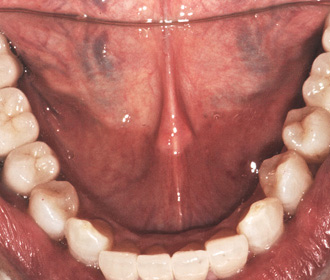

矯正治療、骨移植を伴うインプラント治療、セラミック・クラウン等による機能的、審美的治療

矯正治療、骨移植を伴うインプラント治療、セラミック・クラウン等による機能的、審美的治療

術前